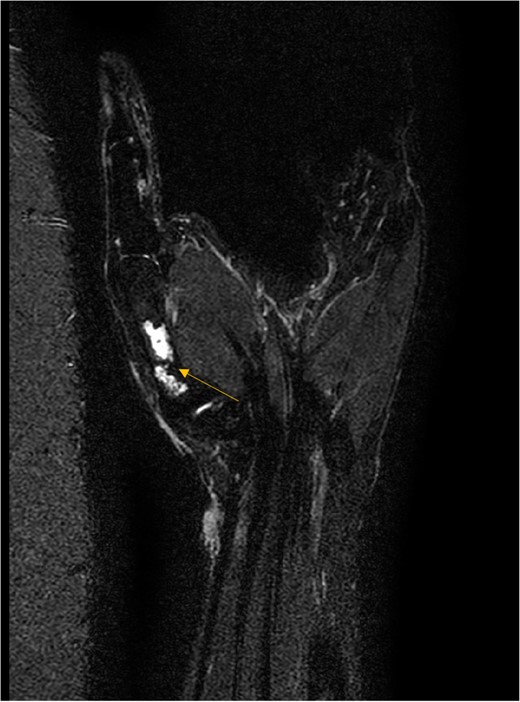

X-ray showed a well-defined non-aggressive lytic bony lesion of the first metacarpal bone (Fig. 1). Magnetic resonance imaging (MRI) showed a grossly stable skin and subcutaneous multilobulated soft tissue mass located at the palmar aspect of the wrist joint measuring 6 × 2 × 3.3 cm3 in its maximum anteroposterior, transverse and craniocaudal dimensions, respectively (Figs 2 and 3). The lesion showed low and high signals in T1 - and T2-weighted images with homogenous contrast enhancement. The lesion was inseparable from the flexor carpi radialis and palmaris longus tendons without definite invasion or encasement. The lesion was not in continuity, however, with the serpiginous lytic bony lesion noted at the first metacarpal bone exhibiting low T1 and high T2 signals with peripheral enhancement and no cortical destruction or associated soft tissue component (Fig. 4).

MRI coronal T2-weighted fat saturated image showing intraosseous lesion of high T2 signal in the first metacarpal bone.